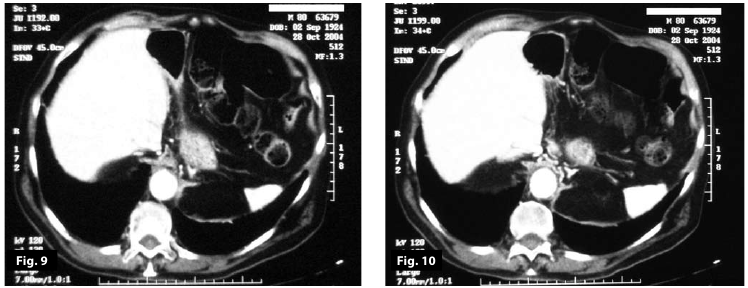

Figure9

Figure10

Figure9-10

Figure5-6-7-8